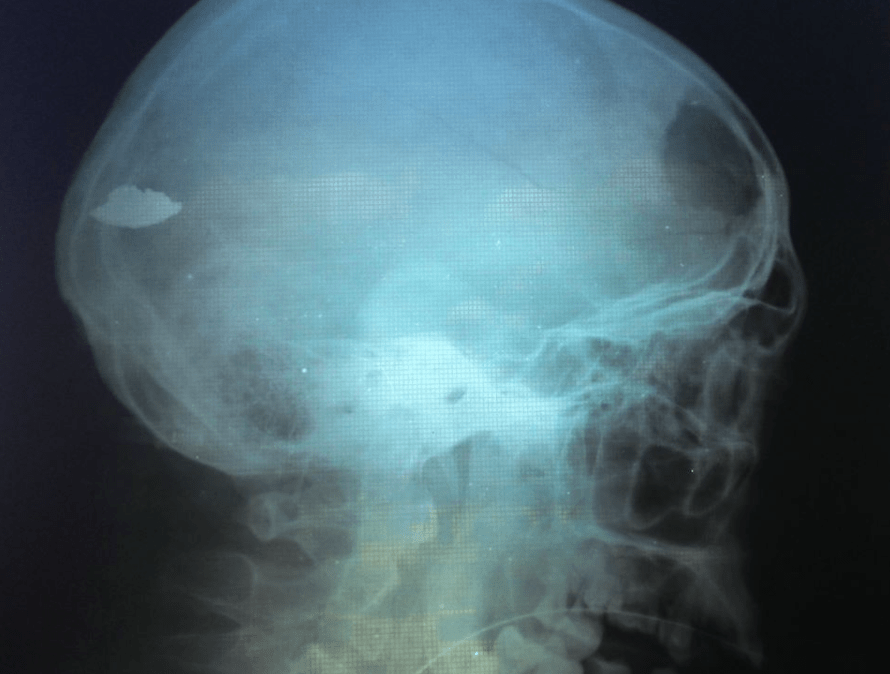

Reports from Mechnikov Hospital: Oleksandr from 93rd Brigade. #FreeSavchenko